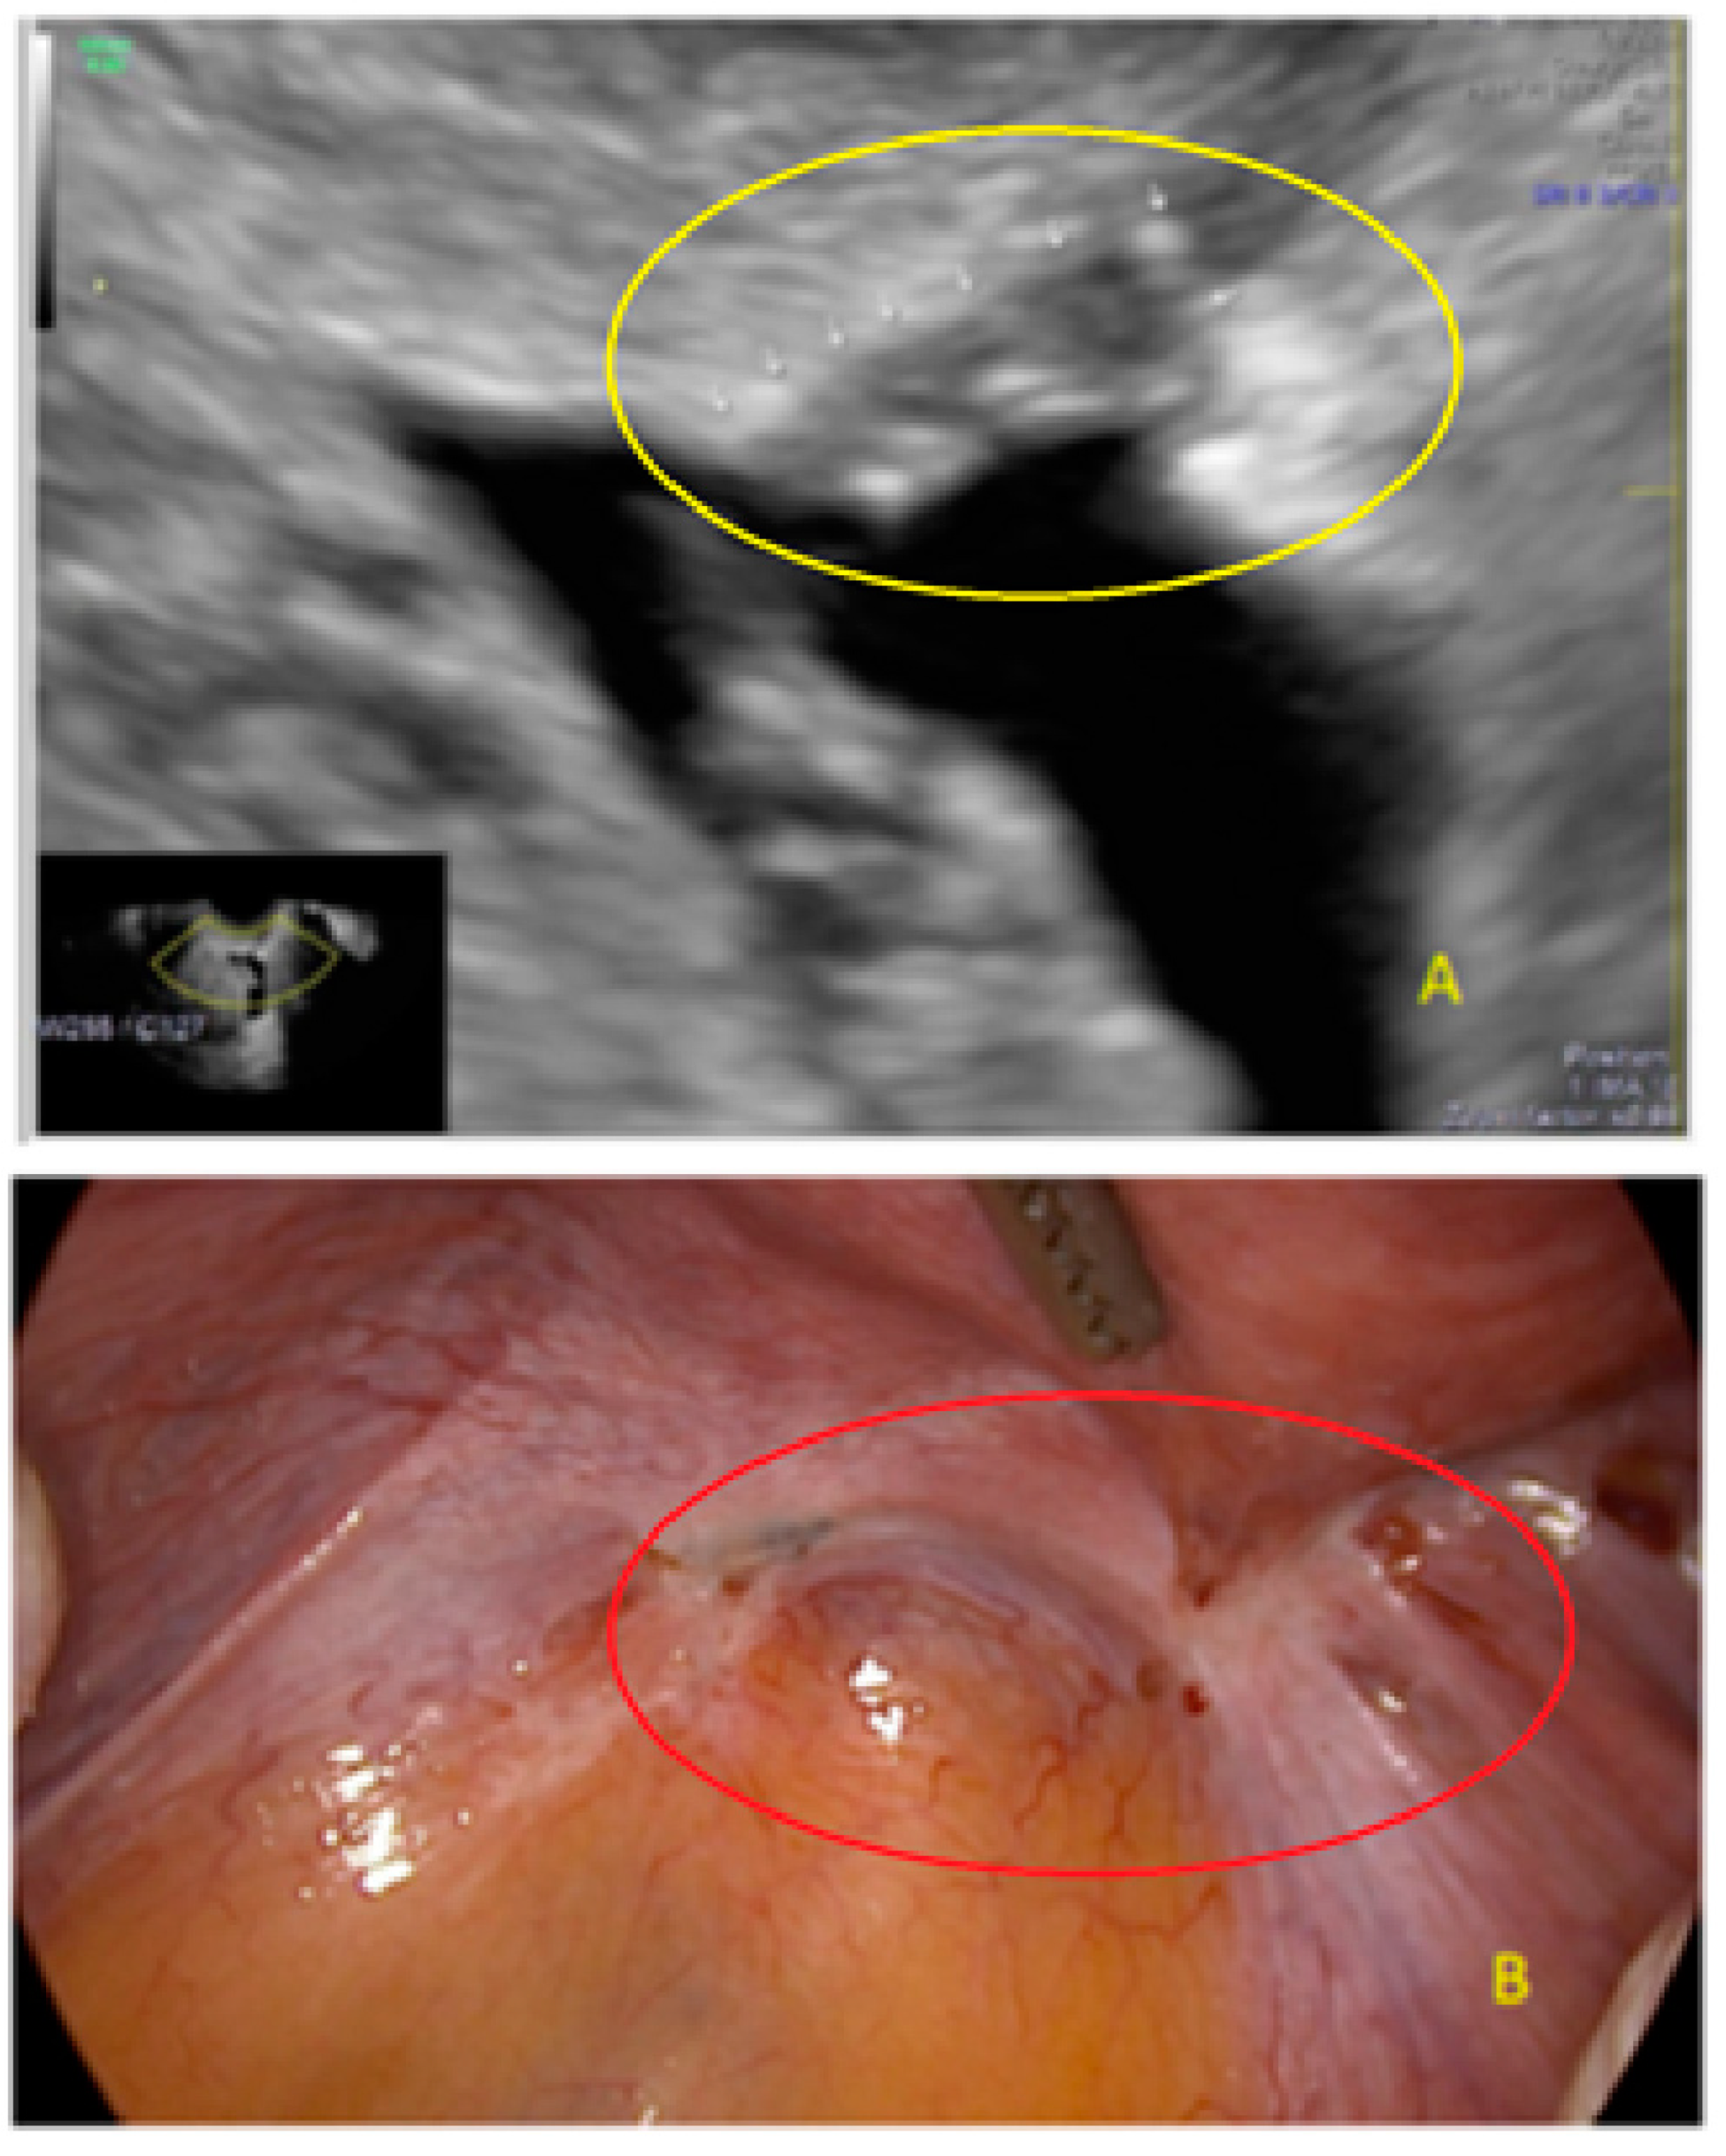

- The presence of hypoechogenic associated tissue (hypoechoic areas surrounding a small cyst area; we called this a “hat”). This tissue does not protrude or invaginate the peritoneal surface.

- The lesion may be convex, protruding from the peritoneal surface into the peritoneal cavity (we called this “bulging”), or it may appear as a concave defect in the peritoneum (we called this a “pocket”).

- The presence of hyperechoic foci (we called this a “pearl”).

- The presence of velamentous (filmy) adhesions associated to the lesion (we called this a “veil”).